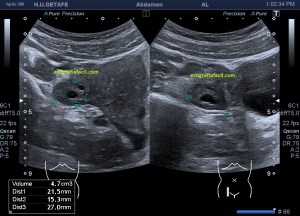

Durante la exploración de una eco de abdomen en el contexto de un paciente que acude por elevación de transaminasas observo una imagen heterogénea, irregular, con una pared marcadamente calcificada, bilobulada de gran tamaño que medí en dos partes ya que me pareció claramente que estaban diferenciadas.

Una de ellas, la primera, era mucho más hiperecogénica y más pequeña, su centro estaba mas calcificado, su sombra acústica posterior era mucho más acuciada y llamaba más la atención. Justo al lado, otra lesión de mayor tamaño, su calcificación era mucho más sutil y más periférica delimitando una LOE hipoecogénica de un tamaño muy importante, adyacente a la más pequeña, como he comentado previamente. Ambas sin señal Doppler.